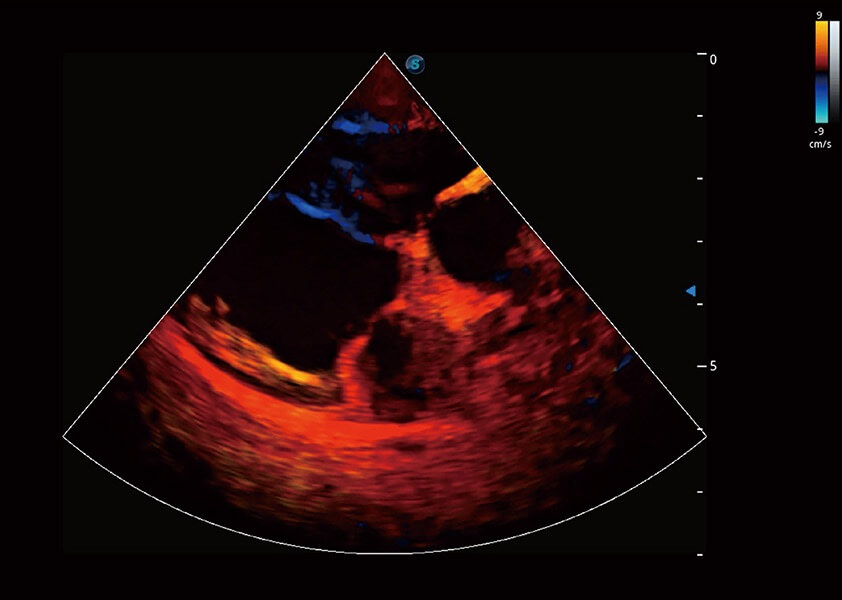

ProPet 60 作为一款高端台式动物超声设备,为动物医生的日常诊断提供了一系列贴合动物临床需求、解决临床实际问题的高级成像功能。凭借全系列高清探头,满足医生对腹部、心脏、生殖、浅表、肌骨等成像的所有需求,切实帮助您提升检查效率,提高诊断信心。

动物是人类最亲密的朋友和最值得信赖的伙伴。狗万官方网站也一直致力于探索动物专用的超声影像解决方案。 全新推出的ProPet系列,是狗万官方网站在动物超声影像智能化、专业化、精准化的一次跨越式革新。动物不能用言语来表述自己的不适,通过超声影像,ProPet系列搭建了动物医生与不同物种沟通的“桥梁”,为动物医生注入了“治愈之力”。